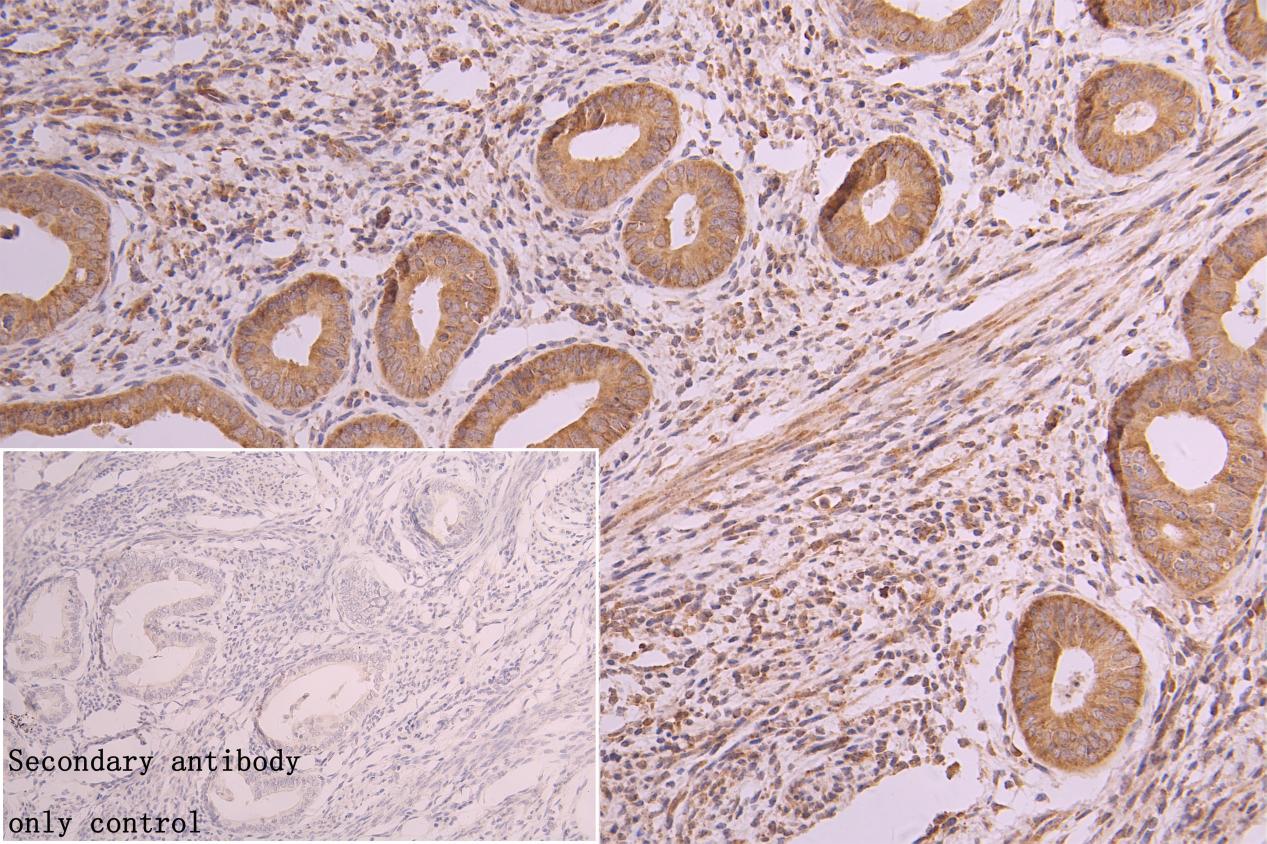

IHC image of CSB-RA827961A0HU diluted at 1:300 and staining in paraffin-embedded human endometrial cancer performed on a Leica BondTM system. After dewaxing and hydration, antigen retrieval was mediated by high pressure in a citrate buffer (pH 6.0). Section was blocked with 10% normal goat serum 30min at RT. Then primary antibody (1% BSA) was incubated at 4°C overnight. The primary is detected by a Goat anti-rabbit polymer IgG labeled by HRP and visualized using 0.05% DAB. Secondary antibody only control: uses 1% BSA instead of primary antibody